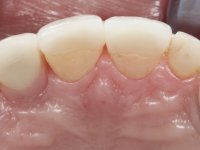

• Colocação de um Implante no local do dente 2.2. Reabilitação do implante com um “abutment” de componente coronário e gengival. em que o orifício de acesso ao parafuso fosse “camuflado” com uma faceta feldspática.

• Reabilitação do dente conoide 1.2 com uma faceta feldspática.

O tratamento iniciou-se com a re -preparação do coto do espigão falso coto fundido, com o objetivo de colocar as linhas de acabamento cervical com uma localização intra-sulcular e simultaneamente confecionar uma coroa provisória adaptada. Com um tratamento ortodôntico muito simples, fechou-se o diastema entre os incisivos centrais superiores e estabilizou-se esta posição com um arame colocado na superfície palatina dos centrais, funcionando como contenção. Posteriormente procurou-se fazer uma tração ortodôntica lenta do dente 2.2 com o intuito de diminuir, ainda que muito ligeiramente a perda óssea vertical nessa zona. Finalizada a tração, foi feita a extração do dente 2.2 e a zona foi reabilitada provisoriamente com uma coroa de resina composta colada aos dentes adjacentes. Foi colocado um implante dentário na zona do dente 2.2 sendo novamente colada a coroa provisória em resina, reabilitando provisoriamente a paciente durante o período de osseointegração. No dente 1.3 foi feita uma gengivectomia com bisturi elétrico, com a intenção de subir o nível cervical do 1.3 conseguindo uma maior harmonia com o dente 2.3. Estabilizados os tecidos moles, foi feita uma impressão com a técnica de moldeira aberta, utilizando silicones de adição de consistência “putty” e “light”. A recolha da cor, tanto da componente dentária como dos tecidos moles foi feita pelo ceramista no consultório.  No laboratório as impressões foram passadas a gesso e deram origem a modelos de trabalho que foram devidamente analisados. Foi decidido confecionar um “abutment” metalo-cerâmico aparafusado sobre o implante. Este “abutment” foi fundido com uma liga nobre e posteriormente revestido a cerâmica coronária e gengival. Dada a inclinação do implante o aparafusamento condicionou de forma inevitável a saída do orifício do parafuso pela superfície vestibular. No sentido de esconder esta situação, o desenho do “abutment” já foi idealizado com a intenção de acomodar na superfície vestibular a colagem de uma faceta feldspática. Este “abutment” foi provado em boca e foram feitos ajustes no componente cerâmico gengival. A sua adaptação aos tecidos moles foi feita tanto de forma subtrativa, com broca, como de forma aditiva, acrescentando resina composta de tonalidade gengival. Este acrescento de resina seria orientador do ceramista na colocação final da cerâmica de tonalidade gengival. A coroa que reabilitaria o dente 1.3 foi cimentada nesta consulta de prova com cimento de ionómero de vidro reforçado com resina composta. Finalizado o trabalho em laboratório da faceta sobre o 1.2 e o “abutment” e a faceta para o implante este foi colado em boca, após a colocação do isolamento absoluto. O trabalho satisfez plenamente a paciente. Durante oito anos a paciente foi seguida regularmente, mostrando-se agradada com o tratamento efetuado, no entanto começou a mostrar interesse em intervir esteticamente nos incisivos centrais superiores. Decidida a segunda fase da nossa intervenção, foi feita a preparação dentária dos dentes 1.1 e 2.1 para a colocação de duas facetas feldspáticas. Particular cuidado foi tido na preparação inter-proximal distal junto ao “abutment” do implante. Foi preciso avaliar muito pormenorizadamente o eixo de inserção da faceta em relação ao “abutment”. As facetas feldspáticas foram confecionadas em laboratório e posteriormente coladas em boca após a colocação de isolamento absoluto. Um ano após, iniciamos a nossa terceira fase de tratamento, após a faceta colada no dente 2.1 ter fraturado. A preparação dentária foi feita sobre a faceta colada, procurando estender mais para palatino o interface inter-proximal distal. O objetivo seria passar para mais palatino do ponto de contacto o interface faceta-dente. O preparo dentário do dente 1.2 também foi muito reduzido, limitando-se a criar um eixo de inserção. Após confecionadas a coroa total e a faceta em laboratório foram coladas em boca. Primeiro foi colada a coroa utilizando-se um isolamento relativo com teflon, posteriormente foi colada a faceta após a colocação do isolamento absoluto. Na coroa utilizei este tipo de isolamento para evitar a utilização de grampos. Seria difícil de aplicar pela forma e dimensão do dente e agressivo para os tecidos moles. Após a colagem foi avaliada a integração oclusal do trabalho.